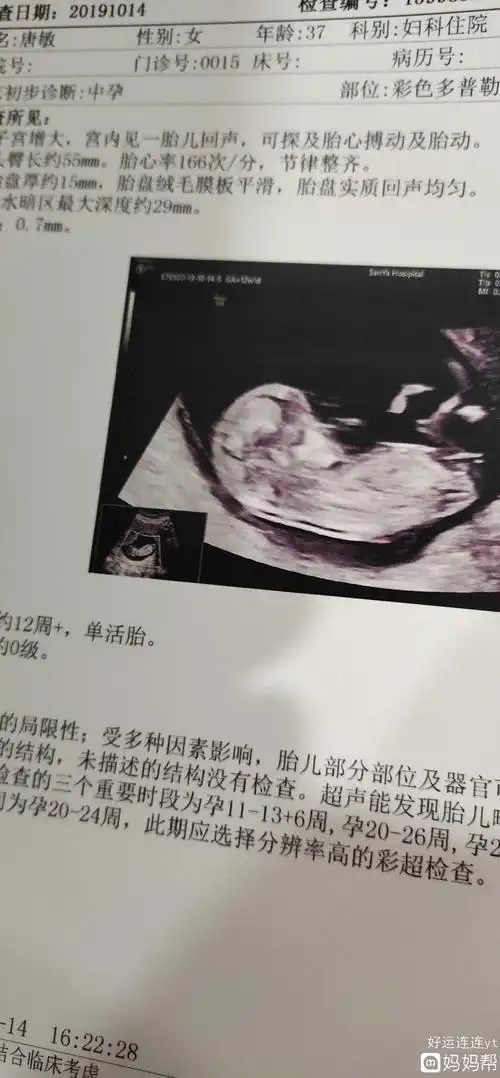

生了女孩的nt图片弯着就是男孩平是女孩吗2

是不是所有的nt图像,有三条线的都表示生女孩呢?

如果nt图是弯着的生男孩,nt图是平行的生女孩